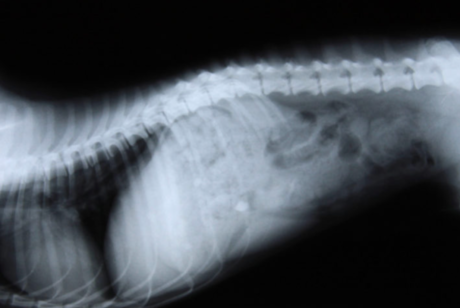

After localizing the lesion area with a physical examination, the integrative veterinarian moves to the next phase of diagnostics, which is radiography. The newer digitized radiographs allow us to see late stage inflammatory changes, but not always all the pathology. If Magnetic Resonance Imaging (MRI) or Computed Tomography (CT) is going to be pursued, generally, surgery will be planned.